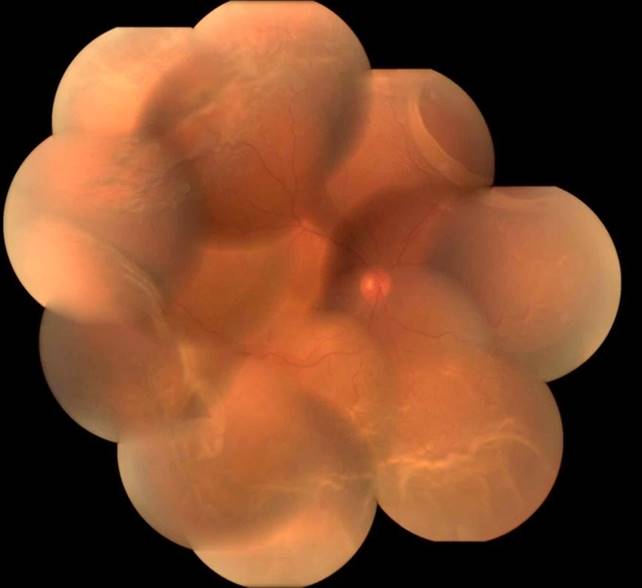

Retina Detachment-:

(Retina Treatment in Delhi NCR)

It is a serious eye condition which causes significant vision loss.

Early signs of Retina Detachment are sudden appearance of Floaters or Flashes or both and Curtain falling or moving across the visual field.

In case any of the above symptoms appear the patient should immediately consult ophthalmologist.

It occurs when fluid accumulates under the retina through a hole or a break which lifts the retina and separates it from underlying layers.

Diagnosis -: Detailed evaluation of the Retina

Treatment -: treatment is only surgical (Scleral Buckle or Vitrectomy)